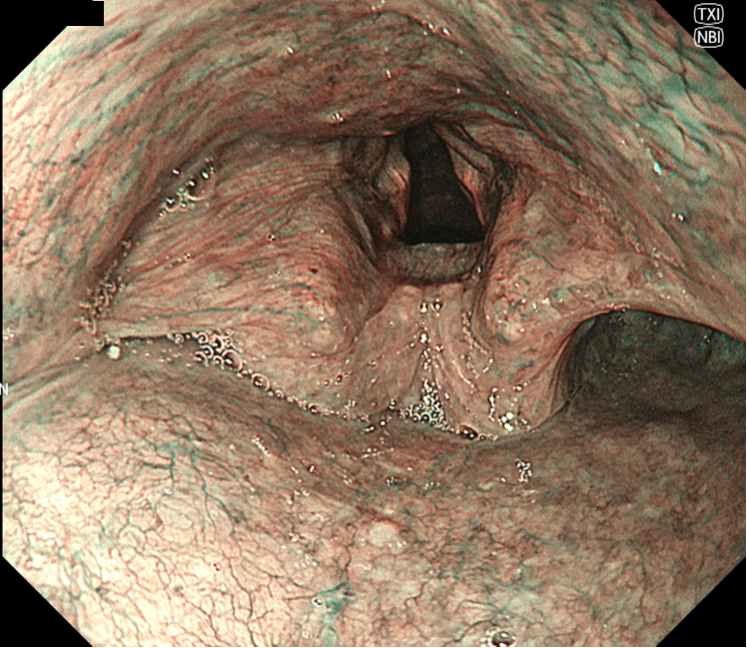

• NBI+TXI観察(中遠景)

切替前 NBI強調設定:B8

NBI+TXIレベル:中

図2 NBI-TXIモード食道病変

食道左壁に管腔の1/3-半周をしめるBrownish areaと血管構造が目立つ領域を認める。